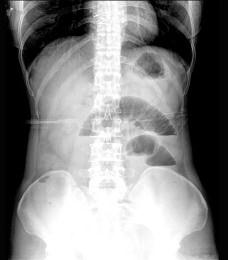

急腹症时用X线腹部透视和摄片可辅助诊断 ( )A、肠梗阻B、胃肠穿孔C、腹腔出血D、不透光胆结石或尿结石E、胰腺炎

问题 急腹症时用X线腹部透视和摄片可辅助诊断 ( )

选项 A、肠梗阻 B、胃肠穿孔 C、腹腔出血 D、不透光胆结石或尿结石 E、胰腺炎

答案 ABD